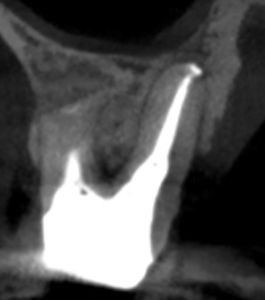

MB

DB

B

問題はないだろう。

#3 MB, DB Apicoectomy 7M recall(2026.3.30)

7ヶ月前と比較した。

劇的に歯槽骨の開創は回復している。